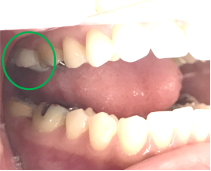

女性 Yさん 60代 (オールセラミック冠)

主訴

以前治療した右下の犬歯が、虫歯になり色が変わってきているので、治したい。

治療内容

根管治療をし、オールセラミック冠を被せました。

所感

神経が取り除かれ、歯自体が変色し、虫歯になっていました。根管治療をし、ファイバーコアを入れ、オールセラミック冠を被せました。

オールセラミック冠1本(失活歯):¥104,500(税込)

Before

After